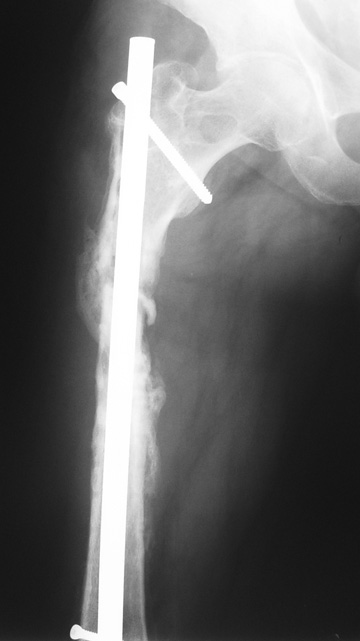

The duration of external fixation (external fixation index) depends on the amount of distraction required, and the extremity is prone to complications during this period. After the distraction phase is completed, the external fixator remains in place during the consolidation phase, which lasts twice as long as the distraction phase; but this period is hardly tolerated. If the external fixator is removed before sufficient consolidation is achieved, fractures, deformity and shortness will be the result. In our department, ‘lenghthening over nail’ method is used in order to decrease the external fixation index and increase patient comfort and activity level. In this method, the intramedullary nail is statically locked after the completion of the distraction phase, and external fixator is removed. The extremity is stabilized by the intramedullary nail during consolidation phase. In this way, complications due to long external fixation index or early removal of the external fixator are avoided.

Case 2